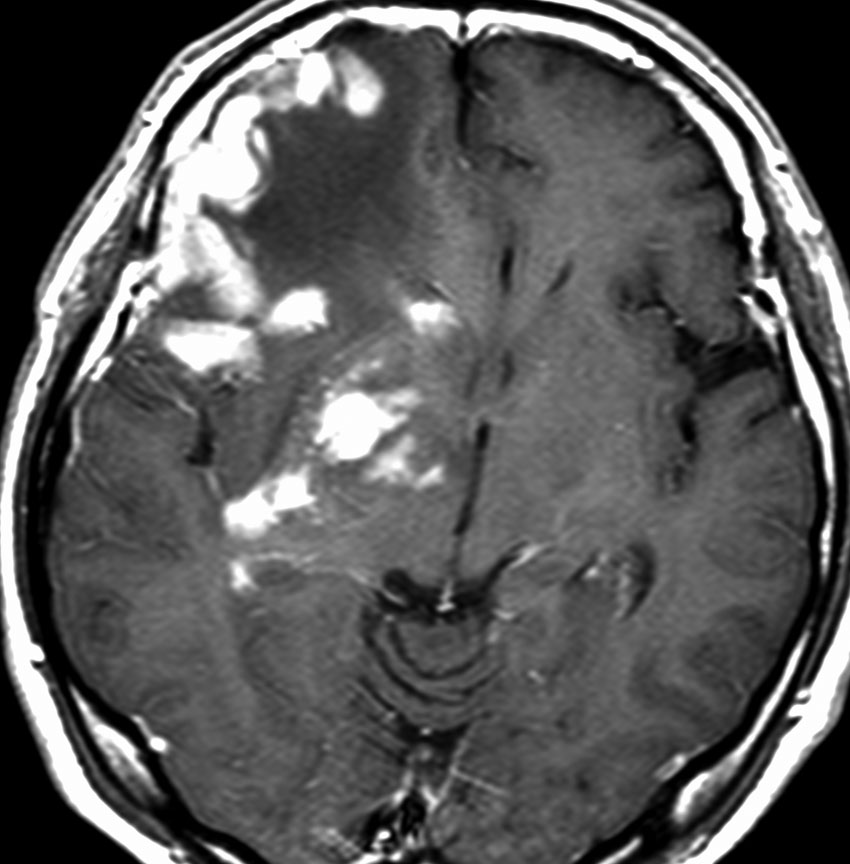

若い患者さんのリンパ腫です。左が診断時MRIで,黄色の矢印でみれる3ヶ所に同時にリンパ腫が発生しています。定位生検術後にすぐにMTX化学療法を3コースしたら,真ん中の画像になりました。ほとんど消失しているのですが,矢印の先にぼーっと少し残っているのでCR(消失)とはいいません。化学療法を終えた後に全脳照射30グレイをしたら右の画像になり治りました。これは順調な治療経過の例です。

矢印の所を定位脳手術で取りました。病理の結果がリンパ腫と確定されましたから,MTX化学療法をしてから放射線をあてたら,右側のMRIのように腫瘍は消えました。患者さんの症状は良くなって退院したのですがーー。

左から,1回目の再発,2回目の再発,3回目の再発です。再発するたびになんとか治療はできるのですが,違った場所に再発してきてだんだん治療が効かなくなってくることが多いです。このような現象から,脳のリンパ腫は脳に発生するのではなくて,体のどこかに原発巣があるのではないかという考えもあります。もちろん、こんな再発をしないで治ってしまう患者さんも多いです。